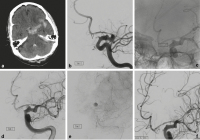

Blister-Aneurysma

Abbildung 6a-c: Die 73-jährige Patientin stürzte zuhause, bei Eintreffen des Notarztes war die Patientin somnolent. Das CT (a) zeigte eine basale Subarachnoidalblutung und die Angiographie bestätigte ein kleines halbkugelförmiges Aneurysma (b). Innerhalb weniger Stunden, unmittelbar vor der geplanten Implantation eines flusskorrigierenden Stents, verstarb die Patientin an einer ausgeprägten Reblutung (c).

Abbildung 7a-f: Der 72-jährige Patient wurde nach einem Sturz mit nachfolgender Vigilanzminderung auswärts intubiert. Die CT bei Aufnahme (a) zeigte eine Subarachnoidalblutung links bis in die insuläre Zisterne reichend. Die Angiographie ergab ein 3 mm großes Blister-Aneurysma der intraduralen A. carotis interna links (b). Das Blister-Aneurysma wurde mit zwei Flow Divertern überdeckt (p64 4,5 × 24 mm und 4,5 × 21 mm, Phenox, Bochum, Deutschland) (c), danach zeigte sich Kontrastmittelstase im Aneurysma (d, e). Aufgrund zunehmender Vasospasmen wurde nach 3 Tagen eine intraarterielle Spasmolyse (Nimotop S, Bayer Vital, Leverkusen, Deutschland) durchgeführt. Dabei zeigte sich das Aneurysma bereits fast vollständig rückgebildet (f).